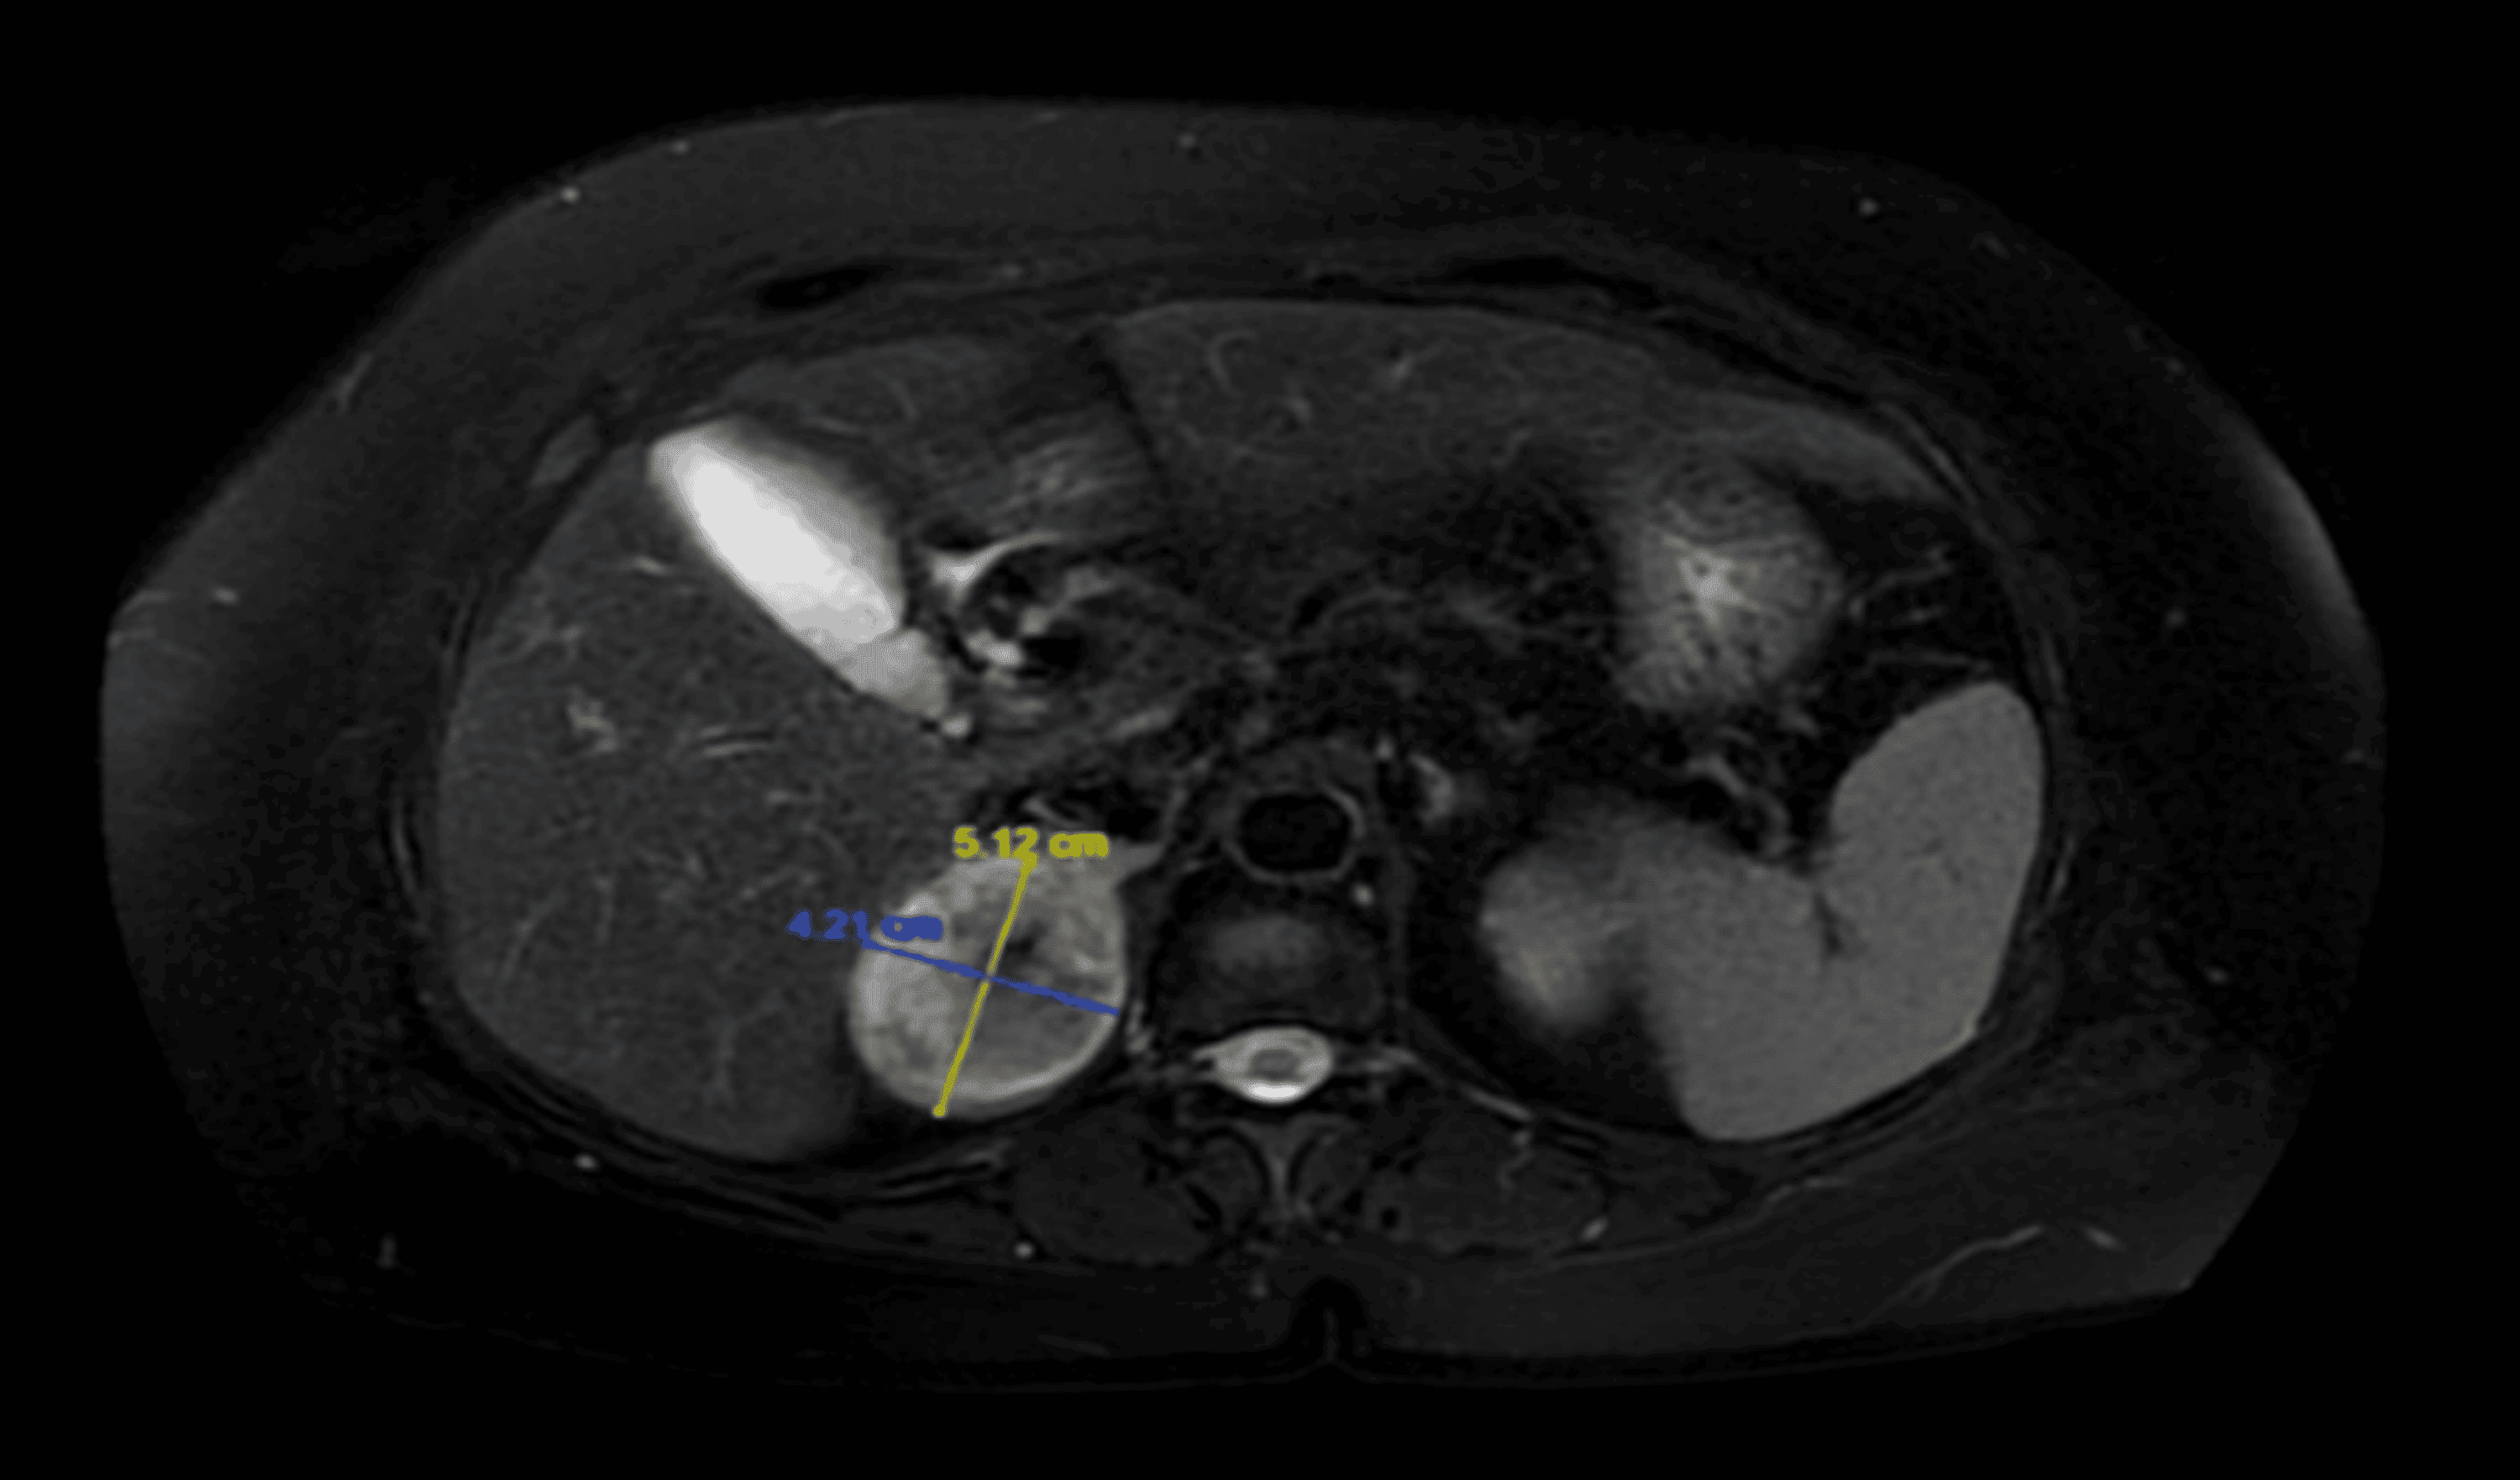

Right adrenal mass. (a) Coronal T2weighted MR image (repetition time... Download HighQuality Adrenal Mass And Weight Loss Pink or purple stretch marks on the skin;. High blood pressure (hypertension) women: There is less pain following the mini back scope adrenalectomy (mbsa). Usually, a pheochromocytoma forms in only one adrenal gland. The most common type is adrenal adenomas, while rarer tumors include pheochromocytomas. Possible symptoms include belly pain, heart palpitations and. Two main reasons that the mbsa lead. Adrenal Mass And Weight Loss.

Rm scan T2 weighted coronal image showing the adrenal mass Download Scientific Diagram Adrenal Mass And Weight Loss Two main reasons that the mbsa lead to faster recovery to normal life after adrenalectomy are: The most common type is adrenal adenomas, while rarer tumors include pheochromocytomas. Usually, a pheochromocytoma forms in only one adrenal gland. If you have an adrenal gland tumor, your symptoms may include: There is less pain following the mini back scope adrenalectomy (mbsa). Signs. Adrenal Mass And Weight Loss.